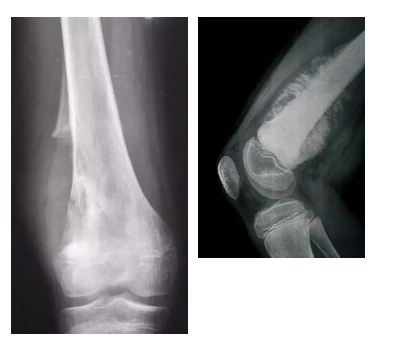

当地医院诊断为“外伤、炎症”,输液进行抗炎治疗两周后,疼痛感越来越重,并出现了骨折。看完X光片,当地医生判断孩子患有“骨纤维结构不良”。辗转求医五个月,亮亮爸妈寻求过中医的帮助,也做了石膏、骨牵引等常规骨科治疗,然而孩子的腿越来越疼,也肿得越来越厉害。

“如果前面几个接诊的医生有骨肿瘤诊疗经验,看到X光片和MR片,做一个简单的穿刺活检,就能尽早发现肿瘤,保住孩子的腿。”沈靖南惋惜地说,像亮亮这样因为家长关心重视不够以及基层医生缺乏经验导致延误病情的情况,并非孤例。

如果孩子有这些情况,家长一定要提高警惕,到医院就诊,并进行照X光片检查。一旦发现异常,通过穿刺活检,多数可以获得明确诊断。